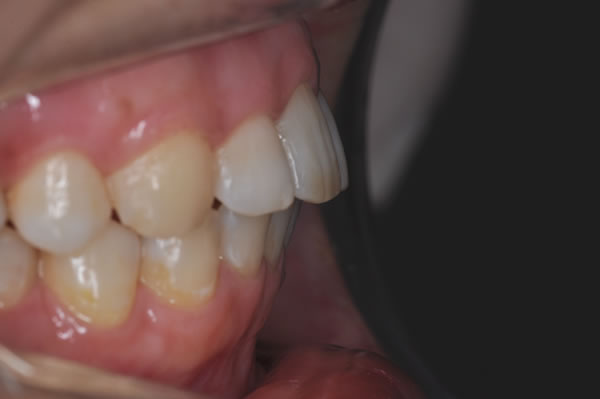

上顎前突症の治療例

上顎前突症(出っ歯)の矯正症例 ケース01

| 治療前(初診) | 治療後 | |